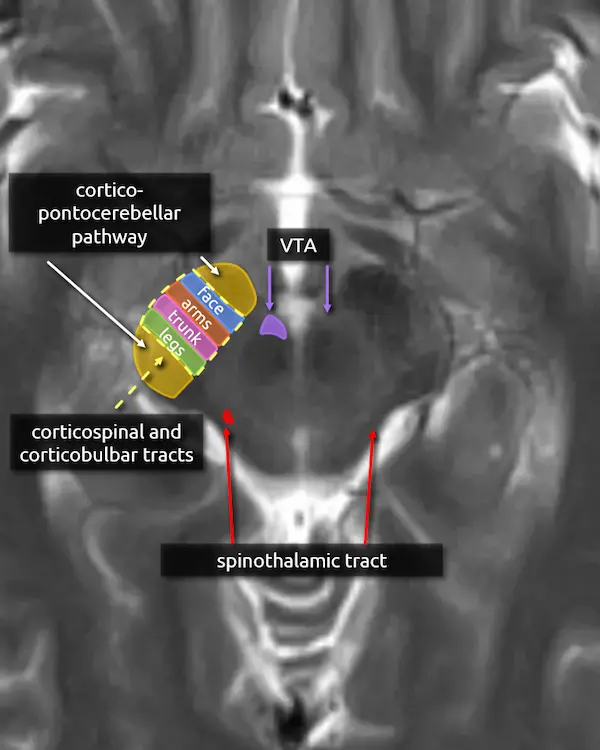

11. Cerebral peduncles (expanded)

The corticospinal and corticobulbar tracts run through the middle third of the cerebral peduncle. Fibers are organized somatotopically; the most anteromedial part innervates the muscles of the face (corticobulbar tract) followed by the arms, trunk, and legs moving posterolateral.

The anterior and posterior thirds of the cerebral peduncle contain tracts of the corticopontocerebellar pathway. Tracts in the anterior component originate in the frontal lobe (frontopontine fibers) and tracts in the posterior component originate from the temporal lobe (temporopontine fibers).

12. Spinothalamic tract

The spinothalamic tract is responsible for pain and temperature sensation. It is found throughout the dorsal brainstem adjacent to the medial lemniscus. Like the medial lemniscus, fibers terminate at the thalamic ventral posterolateral nucleus (VPL).

Fibers of the spinothalamic tract decussate in the spinal cord, so lesions will cause contralateral loss of pain and temperature sensation.

13. Ventral tegmental area (VTA)

The ventral tegmental area (VTA) contains dopaminergic neurons that are involved in reward and goal-directed behaviors. It is found in the medial ventral midbrain in a region called the midbrain tegmentum, introduced below.

Dysfunction of the dopaminergic neurons in the VTA have been implicated in the pathophysiology of addiction, schizophrenia, and depression.